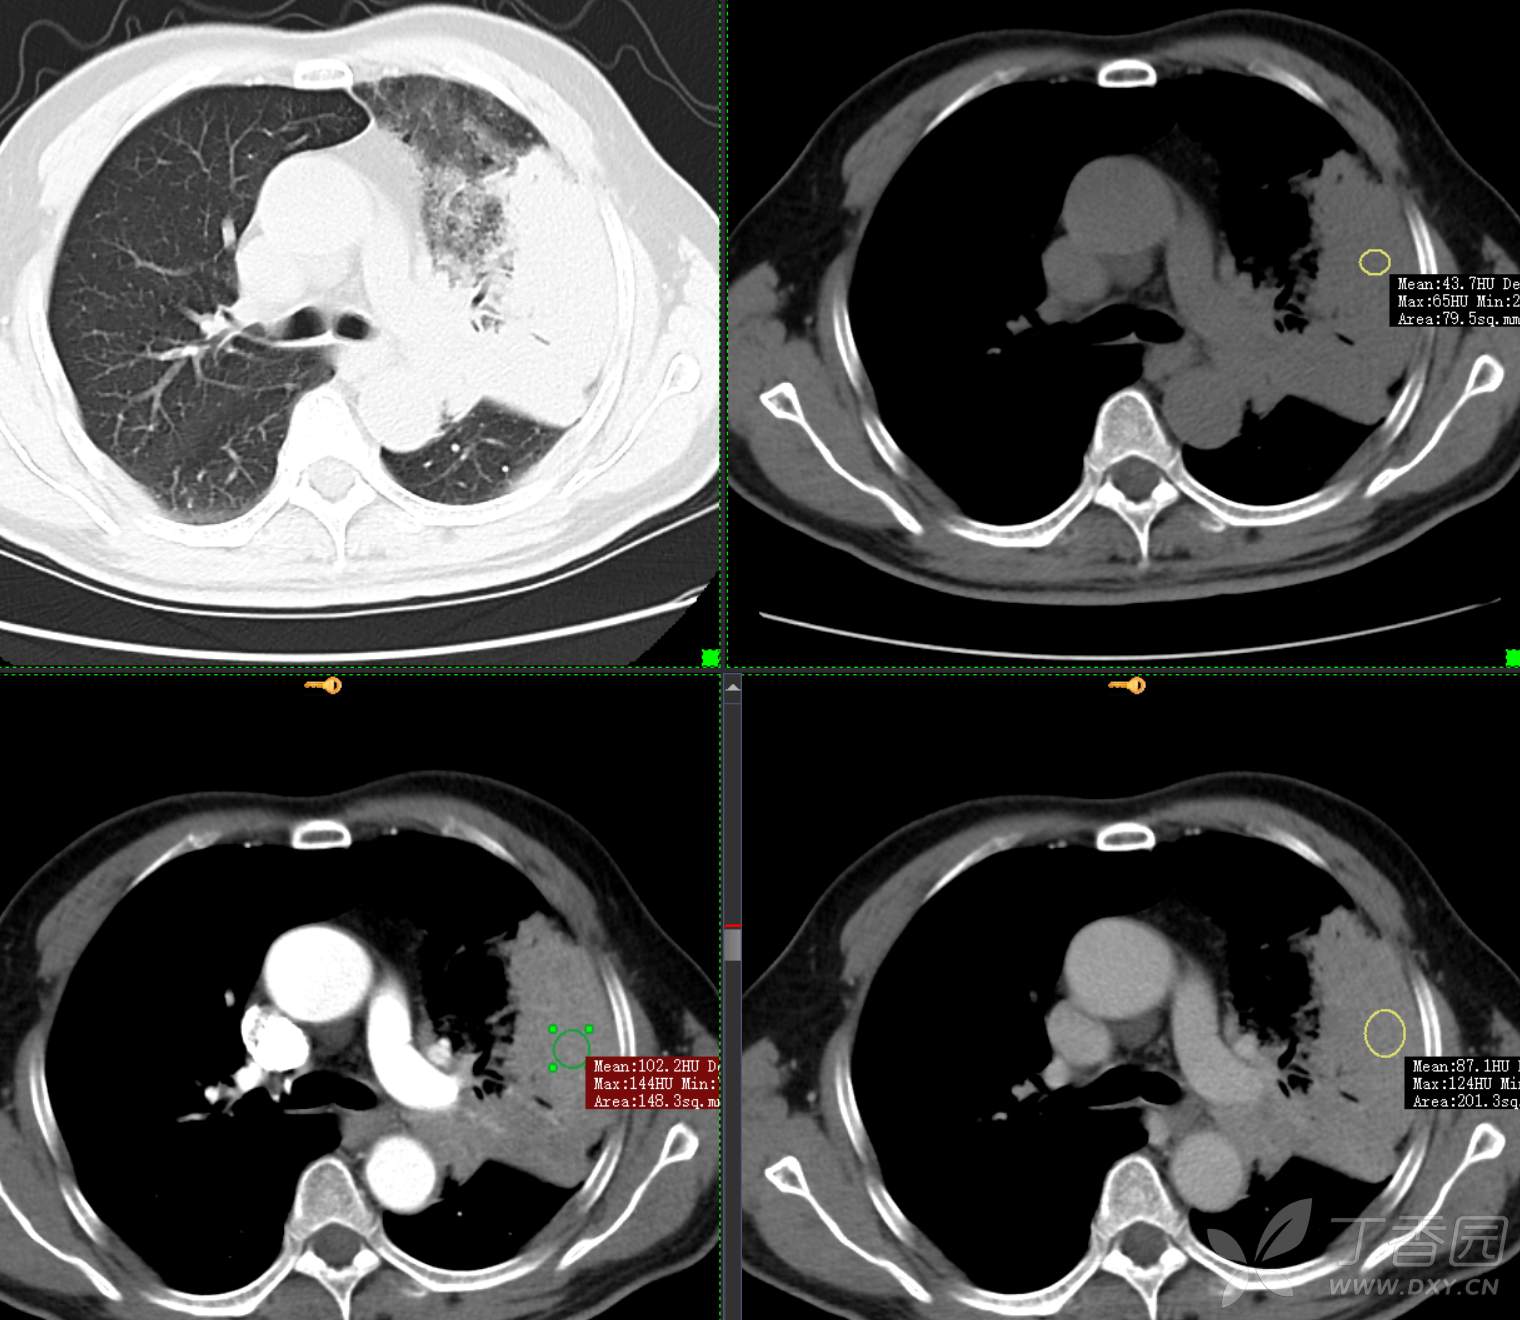

胸部29:大叶性病变,有征象,有特点,你的诊断?

患者性别:男

患者年龄:65

主诉:咳嗽2月余

简要病史:患者2月余前无明显诱因下出现咳嗽,干咳为主,夜间加重,伴咳痰,量中等,白粘痰为主,无明显胸闷气促,无恶心呕吐,无鼻后滴液,无发热畏寒,无鼻塞流涕不话,患者至当地医院就诊,考虑肺部感染,住院治疗,先后予“哌拉西林他挫巴坦针、莫西沙星针、美罗培南针、亚胺培南针、利奈唑胺片”抗感染治疗,患者咳嗽症状稍有好转,但仍存,为进一步诊治至我院门诊,现为进一步诊治,拟“肺部阴影、肺部感染”收治入院。